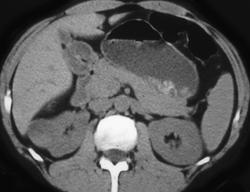

Right Renal Angiomyolipoma